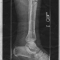

I am not a spider. This was taken at the San Francisco Zoo, and is a good idea of what my leg looked like with the ex-fix in.